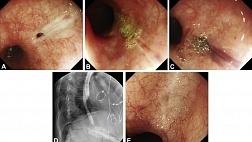

Пациент 72 лет был госпитализирован в стационар с явлениями дисфагии. В ходе гастроскопии обнаружена подслизистая опухоль, располагавшаяся на протяжении 6 см — с 18 до 24 см от резцов (рис. 1 — А). Рентгенокомпьютерная томография показала образование размерами 1,8 см × 5,2 см × 2,9 см в верхней стенке пищевода (рис. 1 — B). По результатам эндоскопического УЗИ стало ясно, что это образование гипоэхогенное и исходит из мышечной стенки пищевода (рис.1 — С).

image001.jpg

Рисунок 1 [1].